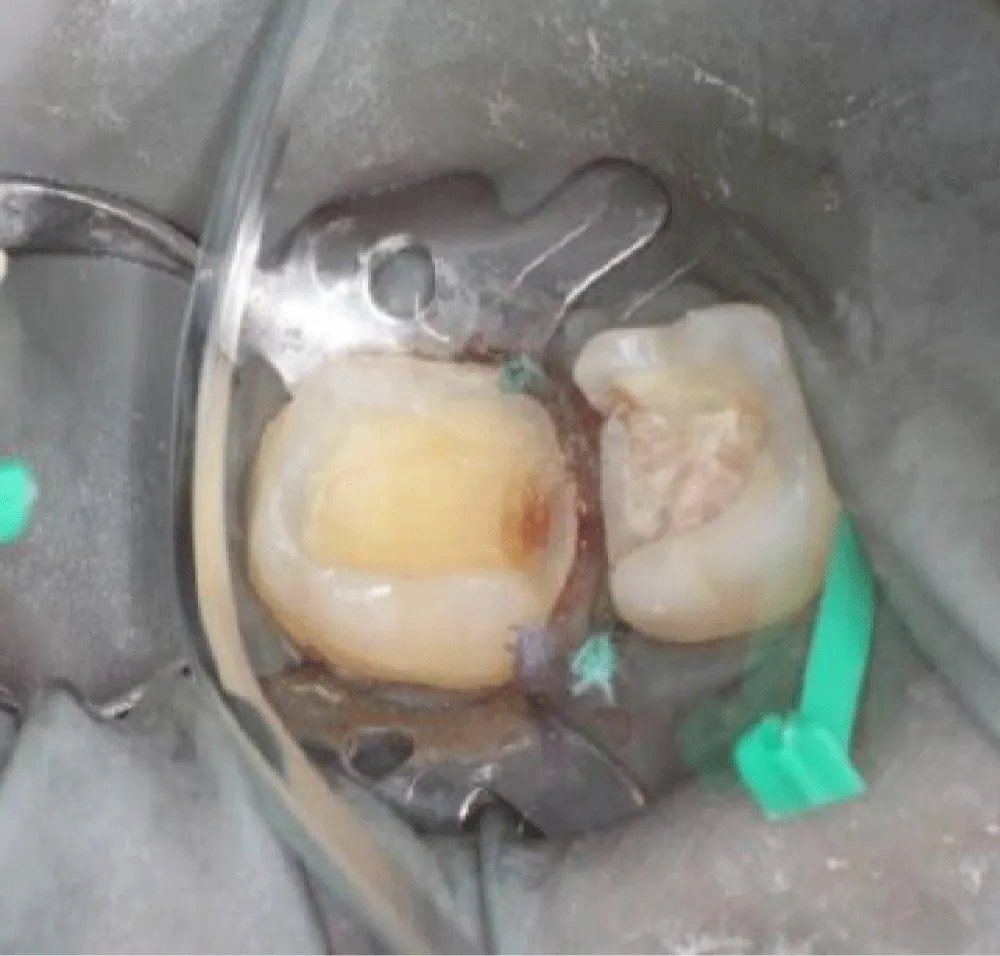

Axial walls in the cavities should be free of undercuts and have a slight divergence (clinical recommendations commonly range from about 6° up to 15° total taper, depending on the system) with rounded internal line angles to reduce stress concentrations. Sufficient tissue thickness on the cusps was maintained (Figure 4).

Sufficient enamel was preserved at the margins because bonded margins to enamel give superior and more durable adhesion. Deep Margin elevation was performed in the first molar. During the stage of cementation, Restorations were etched (hydrofluoric acid for ceramics) and silanized. Tooth surfaces were selectively etched, and a universal adhesive was applied. Duale Resin cement was used for bonding under controlled isolation (Figure 5-7). Restorations were finally light-cured from all aspects, and glycerin was applied in the margins to protect the marginal fit (Figure 8). At the 2-week follow-up, the patient reported complete disappearance of pain. No bleeding was observed during hygiene procedures. The interproximal area was restored, and the architecture was established with a continuous adhesive surface and optimal marginal integrity (Figure 9).